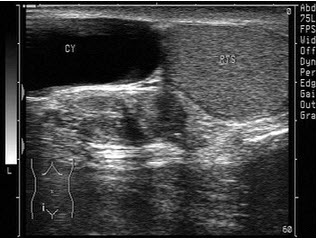

9、单项选择题

患者,男性,甲状腺一侧可触及包块,超声见边界清晰的低回声光团,包膜完整。如图所示,最可能的诊断为()